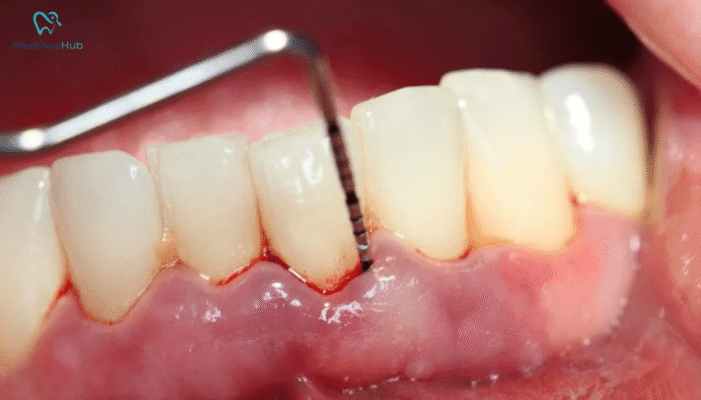

Phân biệt viêm nướu và viêm nha chu chi tiết nhất

Viêm nướu và viêm nha chu là hai bệnh lý răng miệng rất phổ biến...

Cách xử lý viêm nha chu ở bà bầu và cách phòng ngừa hiệu quả

Viêm nha chu ở bà bầu là một trong những bệnh lý răng miệng phổ...

Viêm nướu răng kiêng ăn gì và nên ăn gì để nhanh chóng hồi phục?

Viêm nha chu kiêng ăn gì là câu hỏi thường gặp của những người đang...